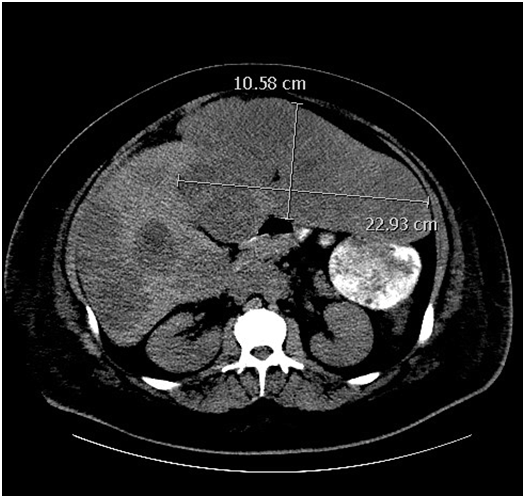

Figure 2 (CT with contrast after therapy).

The patient was in the hospital for 15 total days. Spontaneous renal function recovered one week after admission with creatinine continuing to downtrend to 0.9 at discharge. Bilirubin slowly improved with value of 2.0 at discharge. The patient was seen in outpatient follow-up at our institution to continue care one week after discharge (3weeks after initial presentation). Labs at that point showed tumor marker response with serum B-HCG level of 4150, AFP of 1611, and LDH 1187. Creatinine/Bilirubin at that point were 1.0 and 0.9 respectively. BEP therapy was initiated with plan for 4 cycles. To this point, the patient is tolerating this therapy without unexpected toxicity and has had normalization of serum tumor markers.